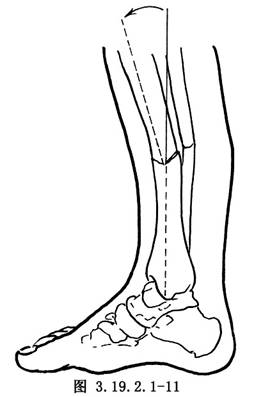

遊離骨端,切除遠、近端硬化的骨組織(圖3.19.2.1-7)。鑽通和擴大遠近端髓腔(圖3.19.2.1-8)。手法矯正脛骨向前成角畸形,並使健康的脛骨遠、近端互相嵌壓。有時需另做切口延長跟腱,以利脛骨成角畸形矯正。如腓骨完整使脛骨兩斷端分離,應另做切口,切除一段腓骨,才能使脛骨兩斷端對正(圖3.19.2.1-9)。以斯氏釘逆行法髓內固定切斷的腓骨(圖3.19.2.1-10)。這樣對脛骨的斷端也提供了良好的對位和固定作用。在手法矯正向前成角畸形時,最好使脛骨矯正到向後成角15°~20°(圖3.19.2.1-11)。